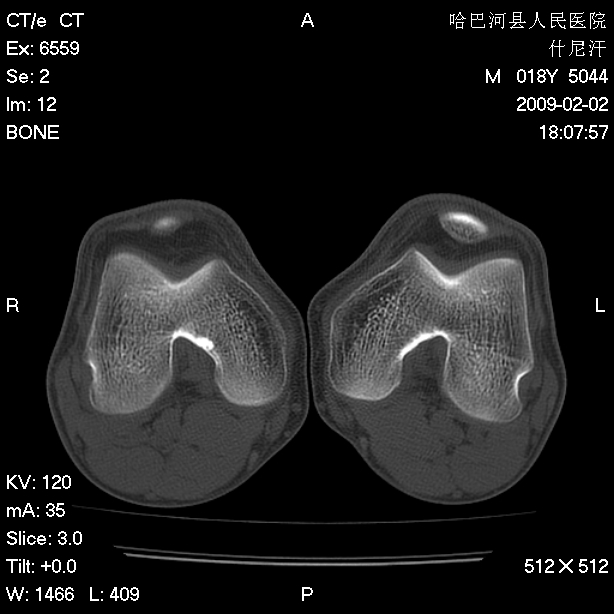

标题: CT17889:外伤后右膝关节反复疼痛3年余 [打印本页]

标题: CT17889:外伤后右膝关节反复疼痛3年余

ct未见明显异常。关节腔未见明显积液,半月板未见明显撕裂。但最好还是mri看看韧带及半月板情况。